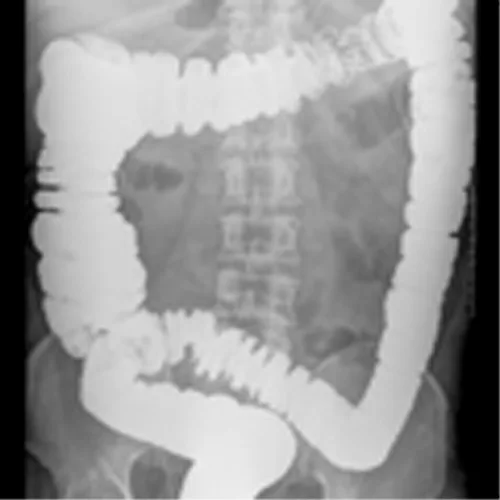

Gastrointestinale

Diagnosi di stipsi secondaria โ Cosa dire al paziente su procedure ed esami